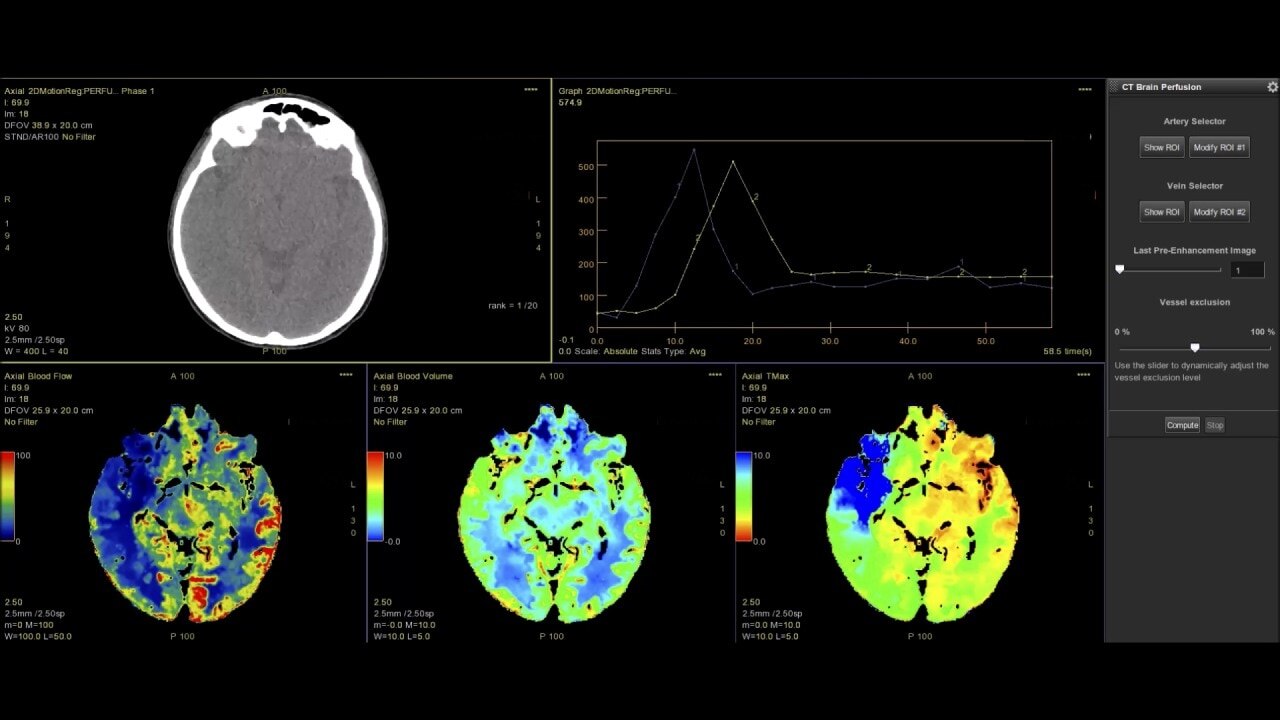

Myocardial perfusion

Complete guided workflow for assessing dynamic CT myocardial perfusion

Dynamic CT Myocardial Perfusion Protocol

The dynamic myocardial perfusion protocol is laid out in a series of three easy to follow steps. Start by selecting the series that has been generated from the non-rigid registration protocol and then follow the guided workflow:

• Cardiac Reformat– images are automatically orientated into short and long axis views

• Segmentation–define the valve plane and the apex of the heart. The software will then calculate the endocardial and epicardial borders and provide a 17 segmented map of the myocardium along with a graphed view for each segment.

• Functional Maps – the third and final step produces the quantitative data with the color overlay and bullseye maps for blood flow, blood volume, mean slope of increase and mean transit time.